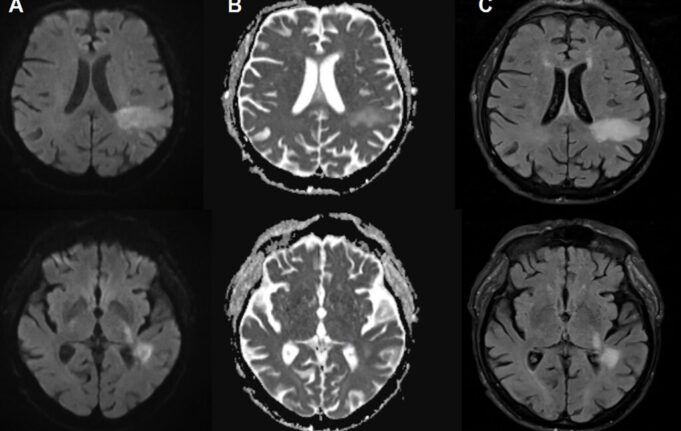

Nella PML, il nuovo virus patogeno, o virus JC “tipo PML”, attacca attivamente il cervello, distruggendo specifiche cellule cerebrali, tra cui cellule Forma la guaina mielinica isolante che protegge le cellule nervose. Ciò porta a un’estesa demielinizzazione, che porta alla disfunzione e alla morte delle cellule nervose. All’imaging, la PML può presentarsi come una lesione caratteristica nel cervello. Queste lesioni illustrate, insieme ai risultati dei test per il DNA del virus JC nel liquido cerebrospinale, rappresentano il modo in cui viene diagnosticata la PML. Ma per i pazienti affetti da leucemia promielocitica, i sintomi possono simulare qualsiasi cosa, dall’ictus alla sclerosi multipla, causando impedimenti nel linguaggio, difetti visivi, disfunzione motoria e convulsioni.